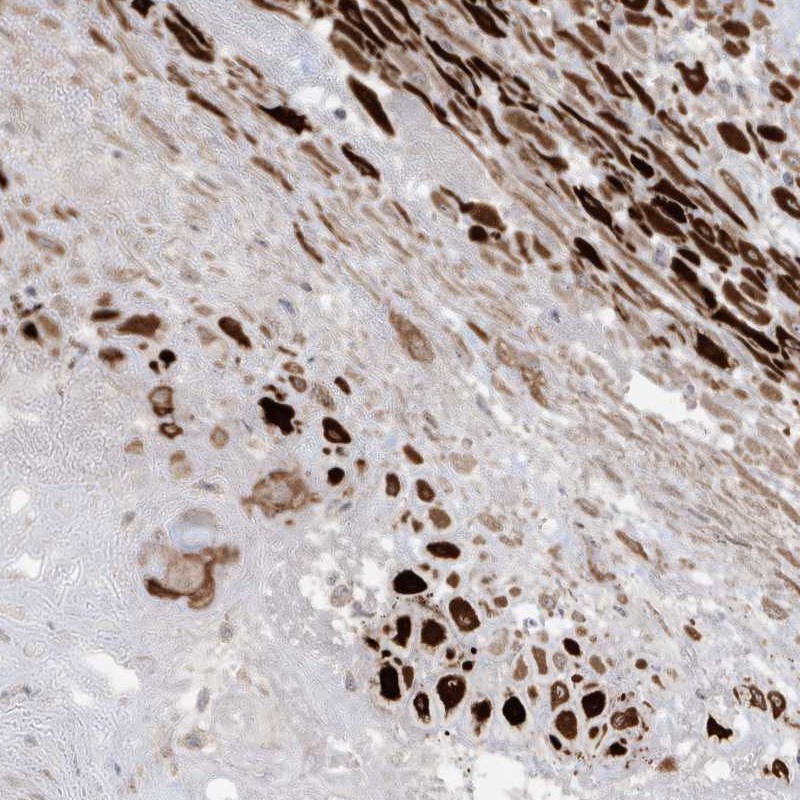

Immunohistochemical staining of human placenta shows strong cytoplasmic positivity in decidual cells.